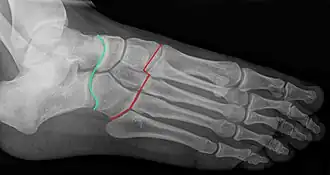

Staw poprzeczny stępu (łac. articulatio tarsi transversa), dawniej nazywany stawem Choparta (łac. articulatio Choparti) – w anatomii człowieka staw złożony kończyny dolnej, obejmujący staw skokowo-łódkowy oraz staw piętowo-sześcienny[1]. Nazwa eponimiczna upamiętnia francuskiego chirurga François Choparta (1743–1795)[2][3].